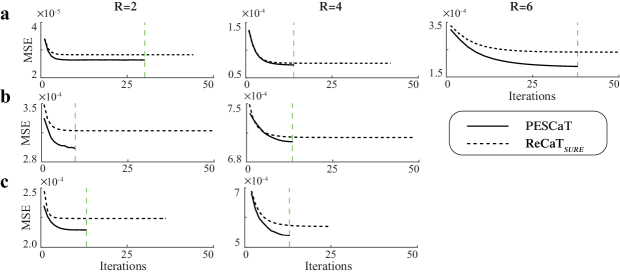

To assess the computational efficiency of self-tuning methods, representative reconstructions were performed for a single cross-section of in vivo bSSFP, T1-weighted, and ToF acquisitions. The true MSE between the reconstructed and fully-sampled reference images were recorded across iterations of PESCaT and ReCaTSURE. MSE curves across iterations are displayed in Fig. 7. Compared to ReCaTSURE, the proposed method converges to a lower MSE value for all R and datasets. Furthermore, PESCaT reduces the number of iterations by 43.3% for bSSFP (average over R=2, 4, 6), 74.5% for T1-weighted (average over R=2, 4) and 53.2% for ToF (average over R=2, 4) datasets. Note that each iteration of PESCaT performs more efficient geometric projections without explicit parameter searches. The reconstruction times for PESCaT and alternative methods are listed in Supp. Table I. On average, the reconstruction time of ReCaTSURE was s for bSSFP, s for T1-weighted, and s for ToF datasets (meanstd. across five cross-sections, average over R=2, 4 for T1-weighted and ToF imaging; R=2, 4, 6 for bSSFP imaging). In contrast, the reconstruction time of PESCaT was merely s for bSSFP, s for T1-weighted, and s for ToF datasets. These results suggest that PESCaT offers up to 10-fold gain in efficiency compared to the alternative self-tuning method ReCaTSURE. While PESSPIRiT yields similar reconstruction times and ReCaTfixed slightly reduces reconstruction times compared to PESCaT, both methods yield inferior reconstruction quality.